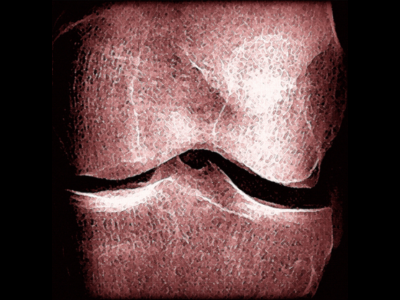

No 22 | Hand mit Ringen (Main avec bague)